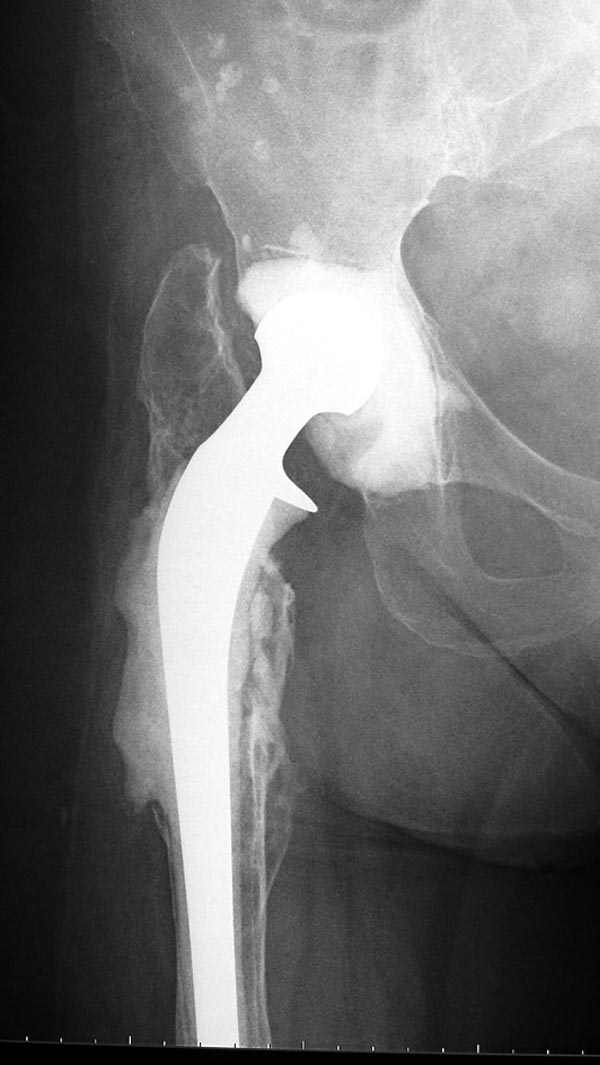

Вот снимки по свежей ситуации, парень 19 лет, длинный оскольчатый перелом бедра от шейки до в-с/3. давно уже ходит на своих ногах.

Представленные Вами рентгенограммы действительно являются примером качественной фиксации спице-стержневым аппаратом. Они, как ни что другое, многое иллюстрируют.

Кроме того, было бы ошибкой ставить знак равенства между нашим и Вашим пациентами. Они не только не похожи, разница между ними просто огромная. Говорю это не для того, чтобы задеть Вас или обидеть. Ни в коем случае. Просто теперь я понимаю, что Ваше мнением строится на простом преломлении Ваших подходов к лечению пациентов со свежими переломами, на ситуацию, абсолютно несопоставимую, подобную нашей.